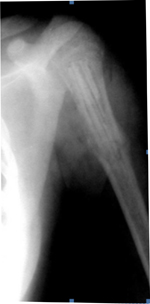

| Рисунок 2. Больная К. 15 лет. Аневризмальная киста левой бедренной кости. Пластика дефекта губчатыми аллоимплантатами: | ||

| а) рентгенологическая картина состояния до операции; | б) состояние после операции; | в) через 3 месяца после операции; |